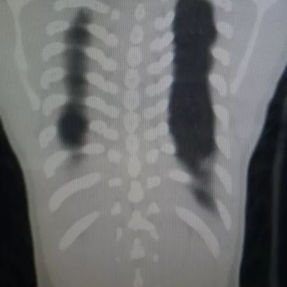

Preoperative Examination

The patient’s anterior chest wall exhibits a prominent depression deformity,characterized by a horizontal groove that affects both sides of the anterior chest wall. There is a surgical scar along the midline and one on the left side, with two scars visible on the right side of the chest wall. A 4x4 cm mass is located on the left chest wall, characterized by darkened skin and noticeable fluctuation upon palpation. The mass extends deep into the intercostal space. Mild scoliosis is also observed. The patient was ultimately diagnosed with grooved chest.

2. Improper bar Placement and Positioning: Preoperative imaging reveals that the bar was positioned along the upper edge of the groove-like depression and was placed at an angle.For optimal support and effective correction of the depressed bony structure, the bar should have been positioned at the base of the depression.

3. Insufficient Number of Bars: In adult patients, the larger chest wall depression and increased bone density generally necessitate the use of at least two bars during corrective surgeries to ensure adequate support and achieve the desired outcome. However, only one bar was used in the patient’s initial surgery, which was insufficient to effectively correct the depression.